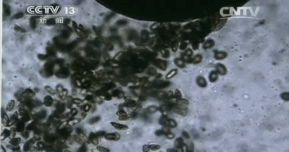

专家说,颚口线虫最容易寄生在黄鳝体内,假如生吃黄鳝,很容易被感染。目前国内并没有研发能痊愈此病的药剂,因此患者康复的几率非常小。千万别生吃黄鳝!